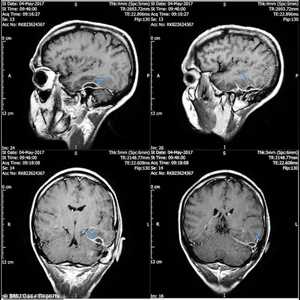

ووفقا لصحيفة نيويورك بوست الأميركية، فقد عمد الأطباء إلى إجراء تصوير بواسطة الرنين المغناطيسي فوجدوا أن دماغ الشاب مليء بما يسمى "الآفات الكيسية" أو مرض "الكيسات المذنبة".

وقرر الأطباء أن الشاب أصيب بمرض اسمه "نيروسيستيسيركوسيس" وهو مرض ناجم عن الإصابة بيرقة "الكيسة المذنبة" التي تتسبب بها الدودة الشريطية التي توجد في لحم الخنزير.